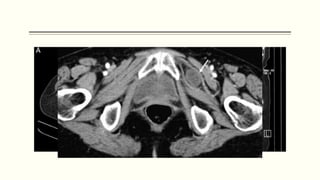

HERNIA OBTURADORA

 Se da por un debilitamiento de la

membrana, que aumenta el

tamaño del conducto.

 Indicios de compresión del

nervio obturador, causante del

signo de Howship-Romberg.

 Es muy probable la incarceración

y estrangulación.

 La mitad de los pacientes

presentan obstrucción intestinal

completa o incompleta.